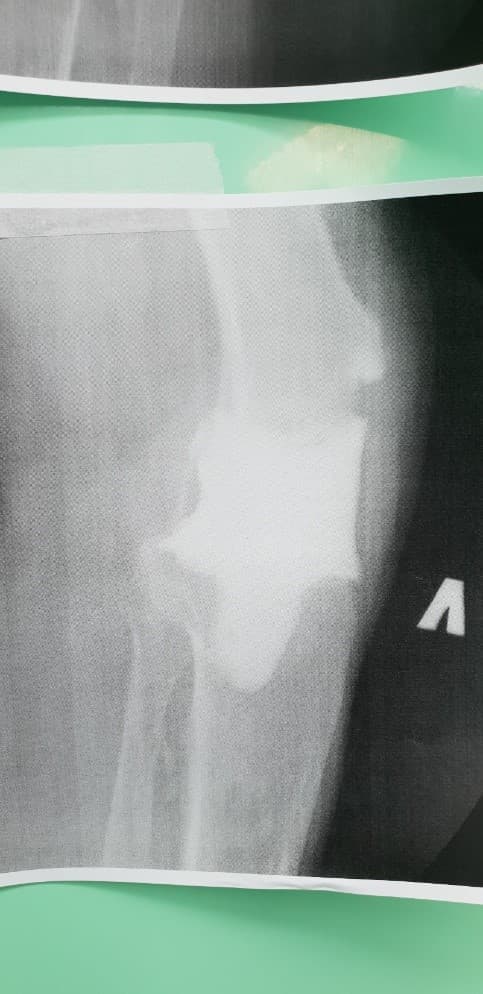

Үе дайрсан ясны анхдагч хавдар, ясны дутмагшлын үед хийгдэх мэс засалimg27Үе дайрсан ясны анхдагч хавдар, ясны дутмагшлын үед хийгдэх мэс засалimg28

Зураг 1. Сэргээн засах мэс заслын өмнөх рентген зураг. Эгц урд, хажуугаас авсан байдал. Халдварын бус шалтгаант хиймэл үений ховхрол.